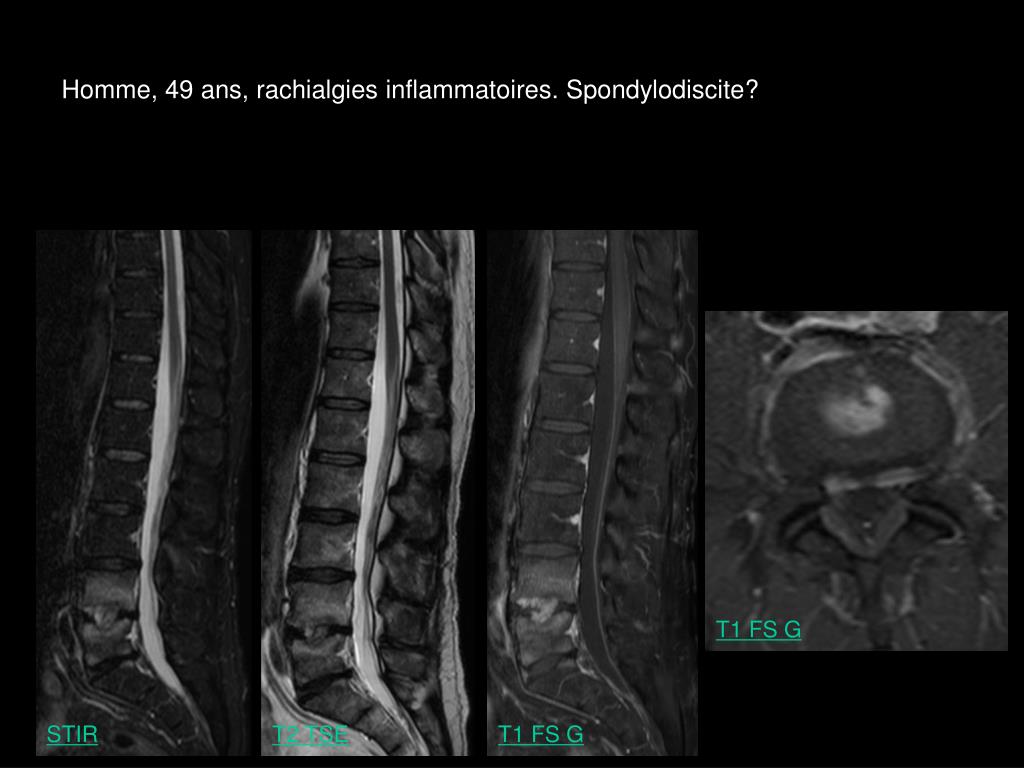

5. Homme, 49 ans, rachialgies inflammatoires. Spondylodiscite? T1 FS G STIR T2 TSE T1 FS G

6. Homme, 49 ans, rachialgies inflammatoires. Spondylodiscite? T1 FS G T1 FS G T1 FS G T1 FS G